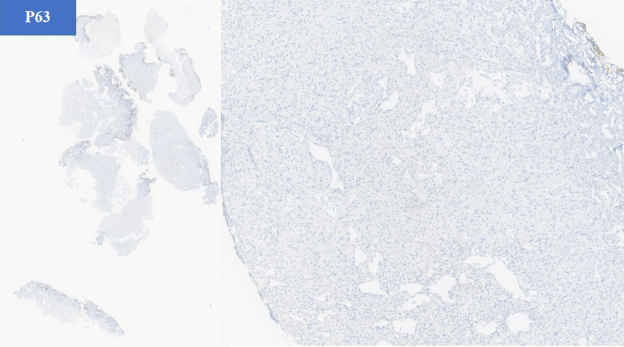

- 尿路上皮标记物:GATA3 (-), P63 (-)

- 上皮标记: PGL 通常不表达 角蛋白(如AE1/AE3)等上皮标记物。